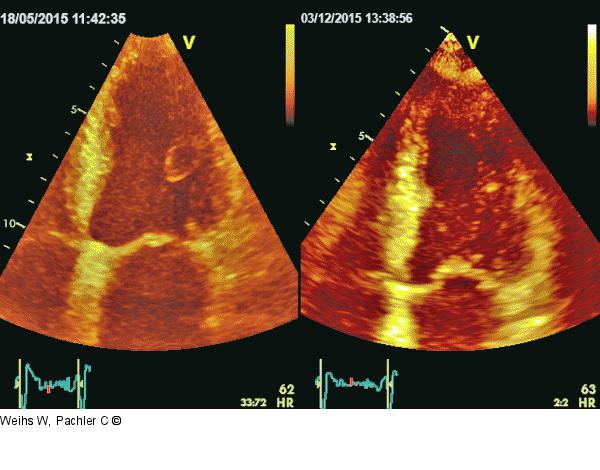

Abbildung 4: Linksventrikuläre Kontraktilität Verlaufskontrolle nach 3-monatiger Therapie: Visuell Besserung der globalen und regionalen linksventrikulären Kontraktilität |

Verlaufskontrolle nach 3-monatiger Therapie: Visuell Besserung der globalen und regionalen linksventrikulären Kontraktilität |